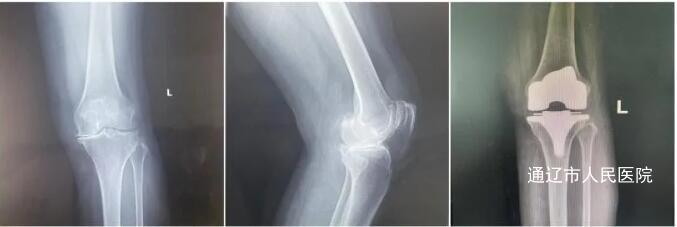

近日,我院关节外科胡中申主任医师团队成功完成蒙东地区首例机器人辅助下关节置换术。这是我院乃至蒙东地区首例应用机器人辅助治疗骨关节疾病,填补了地区关节置换技术的空白,标志着我院骨关节置换技术跨入了关节“智”换的新时代。病例1:患者姜某,女性,62岁,4年前开始出现左侧膝关节肿痛伴活动受限,严重影响日常生活。门诊查体及膝关节X线诊断为:左膝关节骨性关节病。由于患者长年饱受膝关节疼痛折磨,膝关节已明显屈曲伸直障碍,关节间隙消失。胡中申主任医师带领其关节外科团队对该病例进行详细周全地讨论,综合评估患者病情建议实施机器人辅助下左侧全膝关节置换术。得到家属同意后,针对该患者情况,胡中申主任医师团队在文振东主任医师、徐宏顺副主任医师、陈哲主治医师的通力配合下,为其行“机器人辅助下左侧全膝关节置换术”,术中在机器人辅助下实现了亚毫米精确截骨,实时模拟动态监测膝关节伸直屈曲间隙变化,手术全程高效流畅。通过术后测量显示,实际截骨量、植入角度与术前模拟高度一致,真正实现速度与精度的完美结合,大大满足了患者对“个性化”关节置换的需求。术后患者左侧膝关节疼痛明显缓解,功能恢复良好,顺利出院。